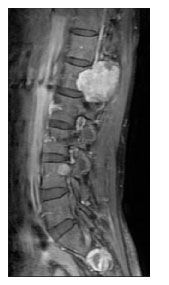

Physical examination revealed right sixth cranial nerve palsy with mild spastic paraparesis. Her CD4+ cell count now was 50/µL, and her plasma HIV RNA level was below 50 copies/mL. A chest radiograph showed an extrapleural mass at the apical area of the right lung (Figure 1). A CT scan of the brain showed an enhancing extradural mass about 4 cm in diameter at the medial part of the right tentorium cerebelli, with erosion of the petrous apex and extension into the right optic canal and prepontine cisterns, encasing the right carotid (cavernous portion) artery (Figure 2). In addition, another extradural mass at the left cavernous sinus extending into the left optic canal and orbital apex was noted. A T1-weighted MRI scan of the spinal cord showed 2 enhancing extradural hypointense lesions about 3 cm and 1 cm in diameter at the right neural foramina of L3 and S1, respectively (Figure 3).

Figure 3.A T1-weighted MRI scan of the spinal cord showed 2 enhancing extradural hypointense lesions approximately 3 cm and 1 cm in diameter at the right neural foramina of L3 and S1, respectively.